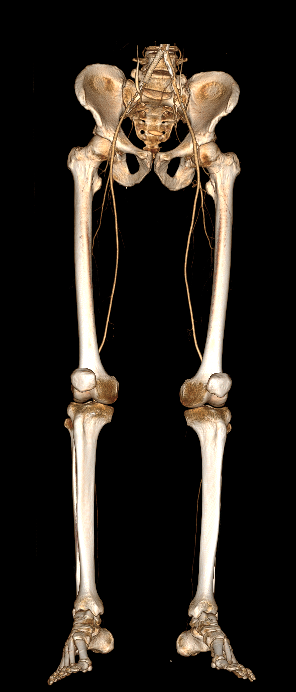

Мультиспиральная компьютерная томография является современным методом обследования сосудистой системы нижних конечностей. Такое исследование по-другому называется КТ-ангиография. Методика позволяет с помощью рентгеновского излучения получить посрезовые снимки и после цифровой обработки создать объемные модели кровеносной системы обеих ног.

В наших медицинских центрах КТ-ангиография нижних конечностей выполняется на современных мультиспиральных компьютерных томографах экспертного уровня TOSHIBA AQUILION. Аппараты послойно сканируют область исследования, одномоментно выполняя множество тончайших срезов. В результате получаются снимки высокого качества и трехмерные модели с изображением даже мелкой сосудистой сети нижних конечностей. При этом методика скоростного мультисрезового сканирования обеспечивает минимальную дозу рентгеновского облучения для пациента.

• КТ сосудов от бифуркации аорты до коленного сустава (оценивается нижняя часть брюшной аорты, разветвление аорты, подвздошные артерии, бедренные и подколенные артерии)

• КТ сосудов от бифуркации аорты до стопы (данный протокол обследования включает в себя полное обследование сосудов нижних конечностей, включая стопы)